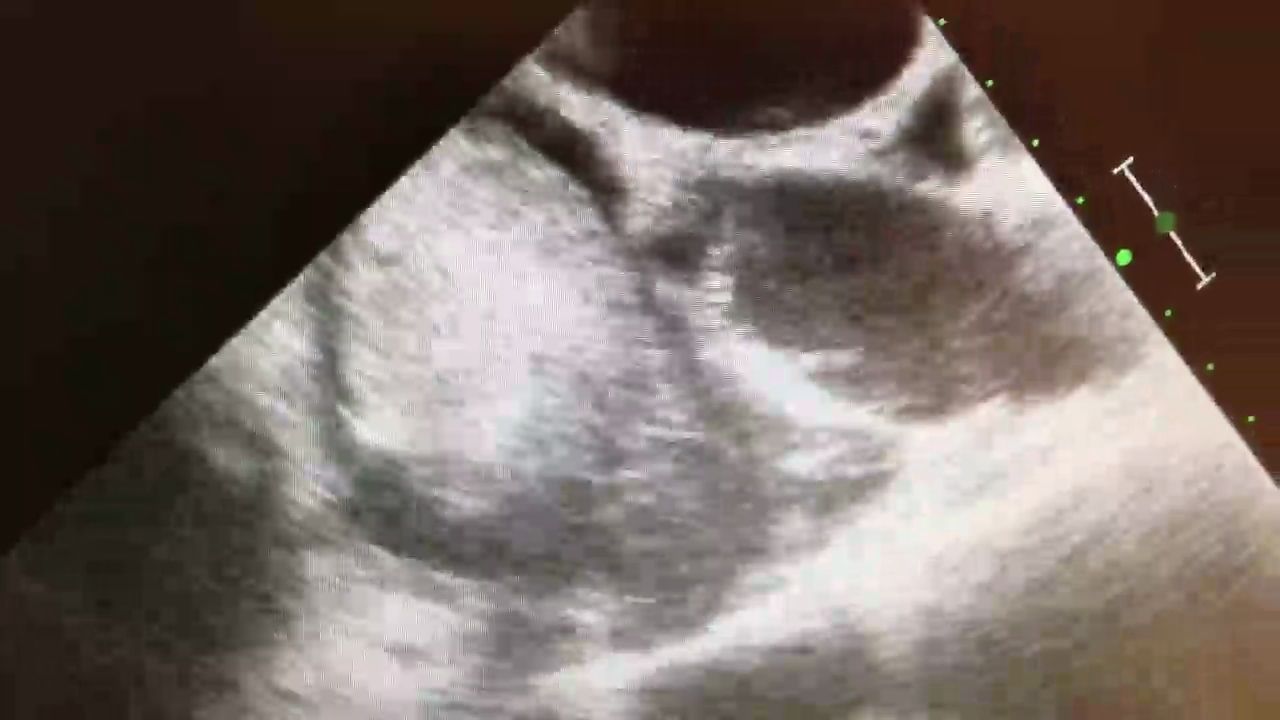

65 y/o male presents to his primary care physician with CC of lower extremity edema, dyspnea and near syncope events that have been going on for several months.

Pmhx: Smoker, CAD, hyperlipidemia, HTN.